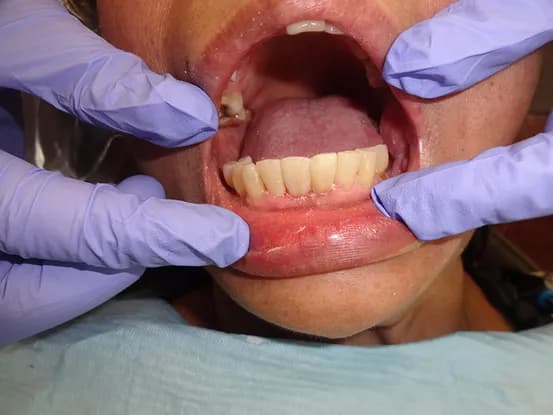

Case 11

62 year old female with overbite and multiple worned and discolored teeth and wanted a dental cosmetic makeover. 3 quadrants osseous surgery, crown lengthening and 20 units of E-Max restorations performed to restore smile to a more youthful look.